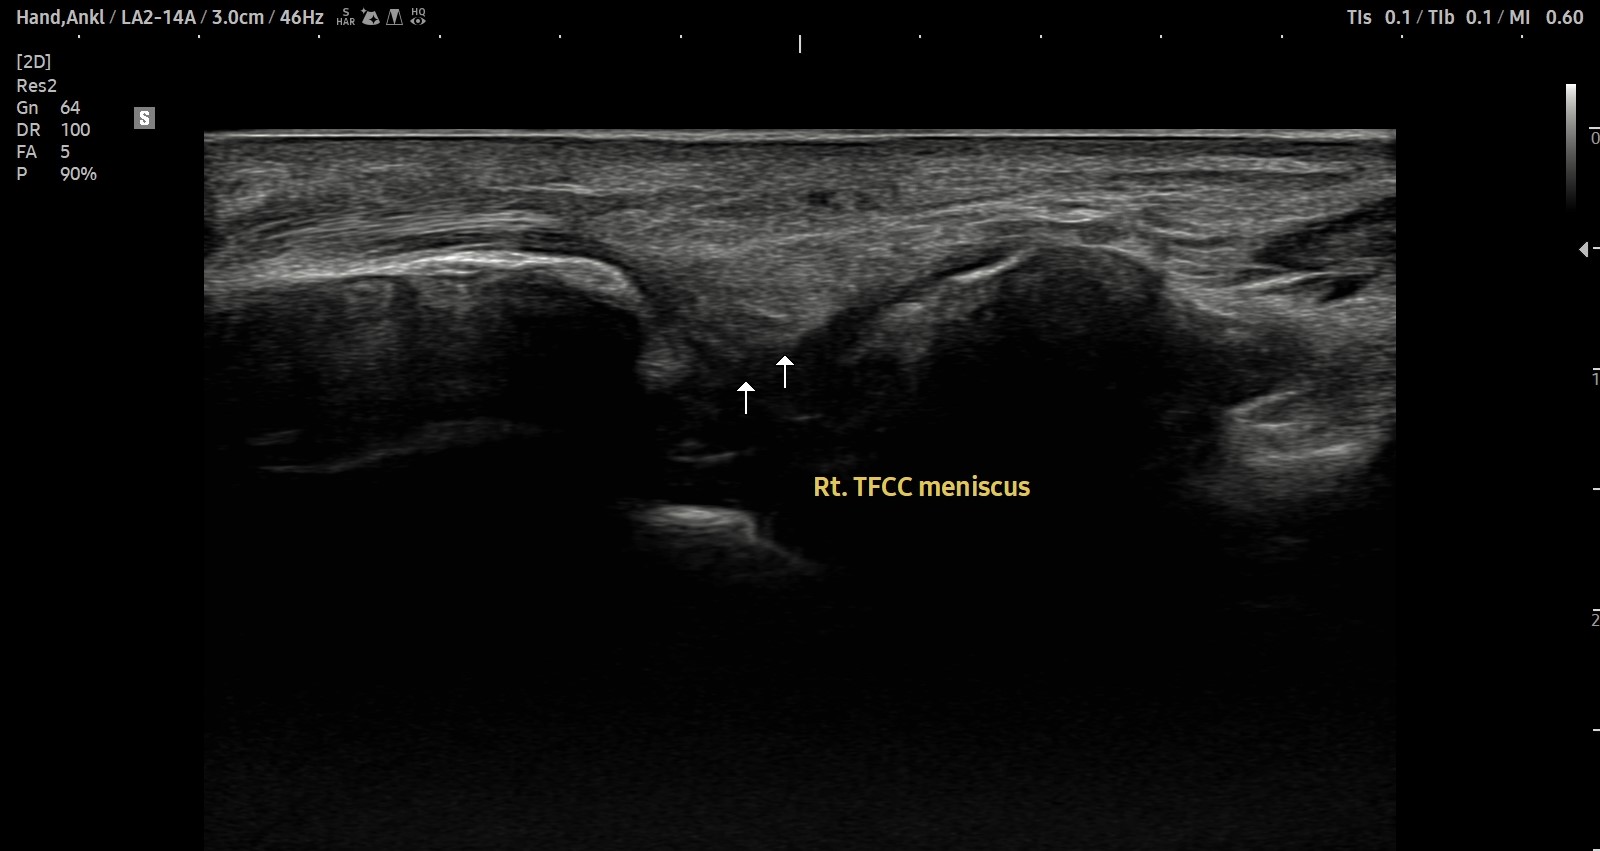

치료 후기에 사용된 전/후 검사 사진은 동일 인물의 결과이며 각 지점 동일 조건에서 촬영되었습니다.

개인에 따라 치료 결과에 차이가 있을 수 있으며, 부작용이 발생할 수 있습니다. 내원 후 충분한 상담을 받으시고 치료를 진행하시면 됩니다.

- 치료기간 : 2025. 5. 1. ~ 2025. 6. 14

- 치료횟수 : 10 회

[치료 전]

[치료 후]